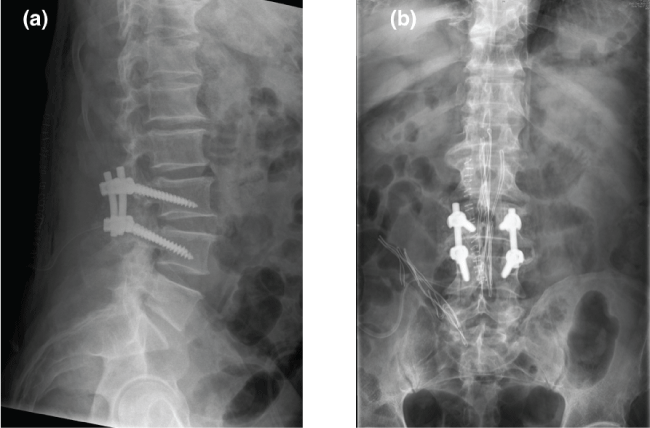

As conservative treatment does not work surgical we decided to do surgical treatment, performing hemilaminectomy L3, left yuxtafacetaria excision of tumor (Figure 2), foraminotomy, release the left L4 root and fusion of L3-L4 (Figure 3).

Figure 2: (a,b) Intraoperative photographs demonstrating the cyst in situ; (c) Cyst.